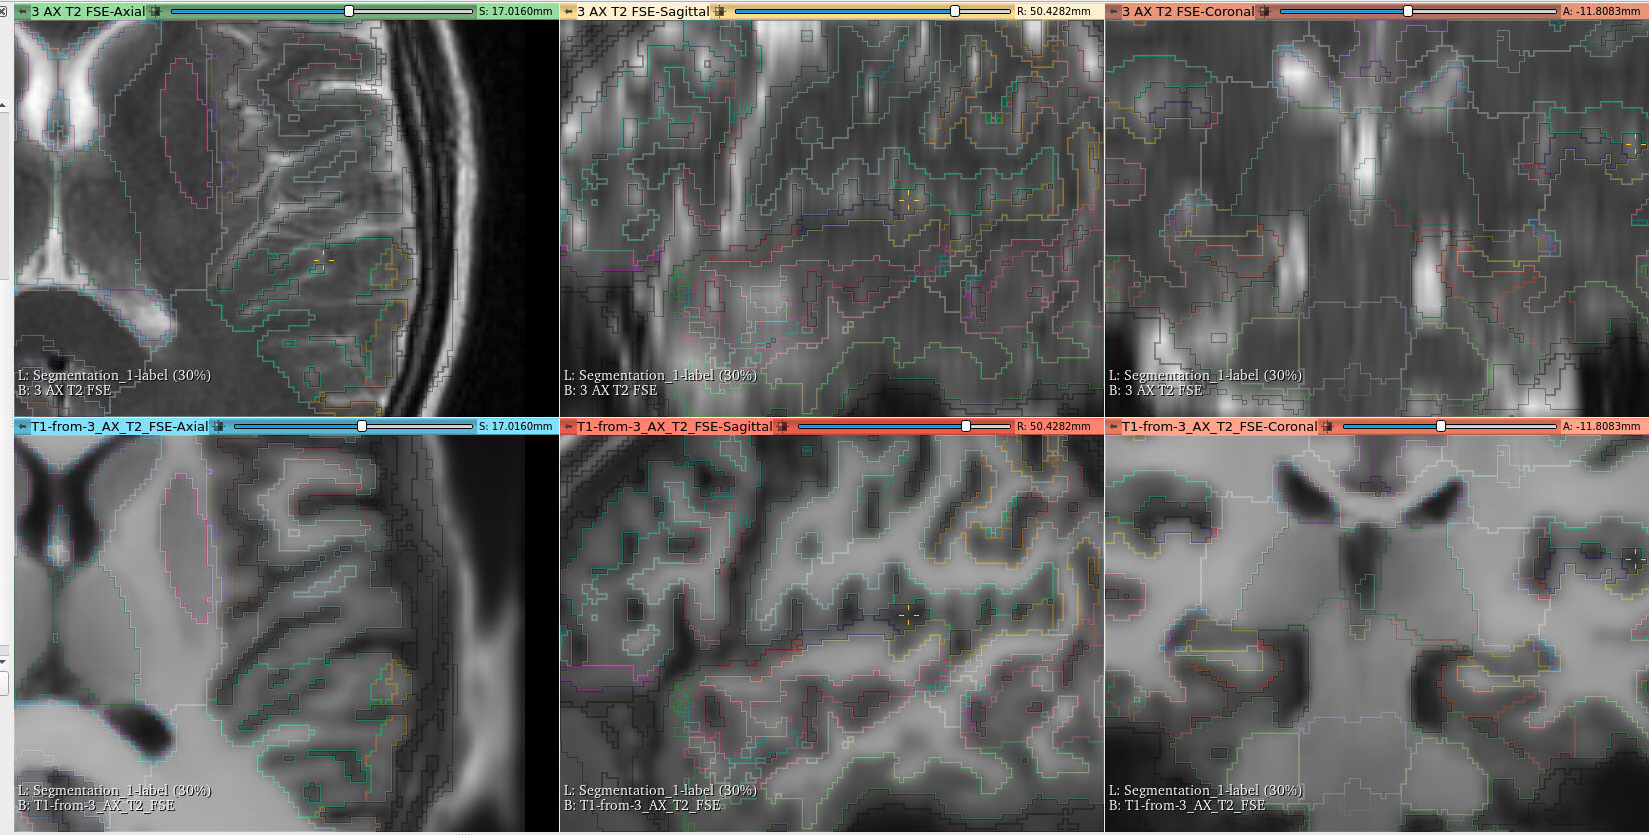

Brain Resection Cavity Segmentation

Based on Pérez-García et al., 2021, A self-supervised learning strategy for postoperative brain cavity segmentation simulating resections. More info at the resseg-ijcars repository.

Brain Parcellation

Based on Li et al., 2017, On the Compactness, Efficiency, and Representation of 3D Convolutional Networks: Brain Parcellation as a Pretext Task. More info at the highresnet repository.